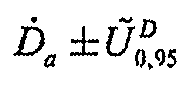

6.8. Результаты измерений заносят в протокол измерений в виде:

,

,

6.9. Рекомендуемая форма протокола дозиметрического контроля представлена в приложении к настоящим МУК.